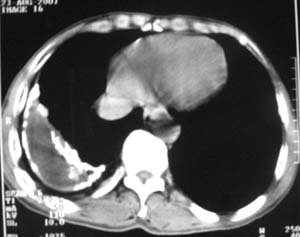

男,54岁,无任何不是感.体检发现右肺部阴影.现行ct进一步确诊.

右侧胸廓塌陷,肋间隙变窄,肋骨增生变粗,脏壁层胸膜肥厚、钙化。符合陈旧性结核性脓胸改变

右侧包裹性积液伴胸膜钙化.

右侧包裹性积液并胸膜钙化,性质还是结合穿刺细胞学检查的好,结核性、化脓性均会有钙化。

右侧胸膜肥厚、粘连、钙化。

周围都钙化了应该不是积液了吧,这样都没有不适感,病史不详